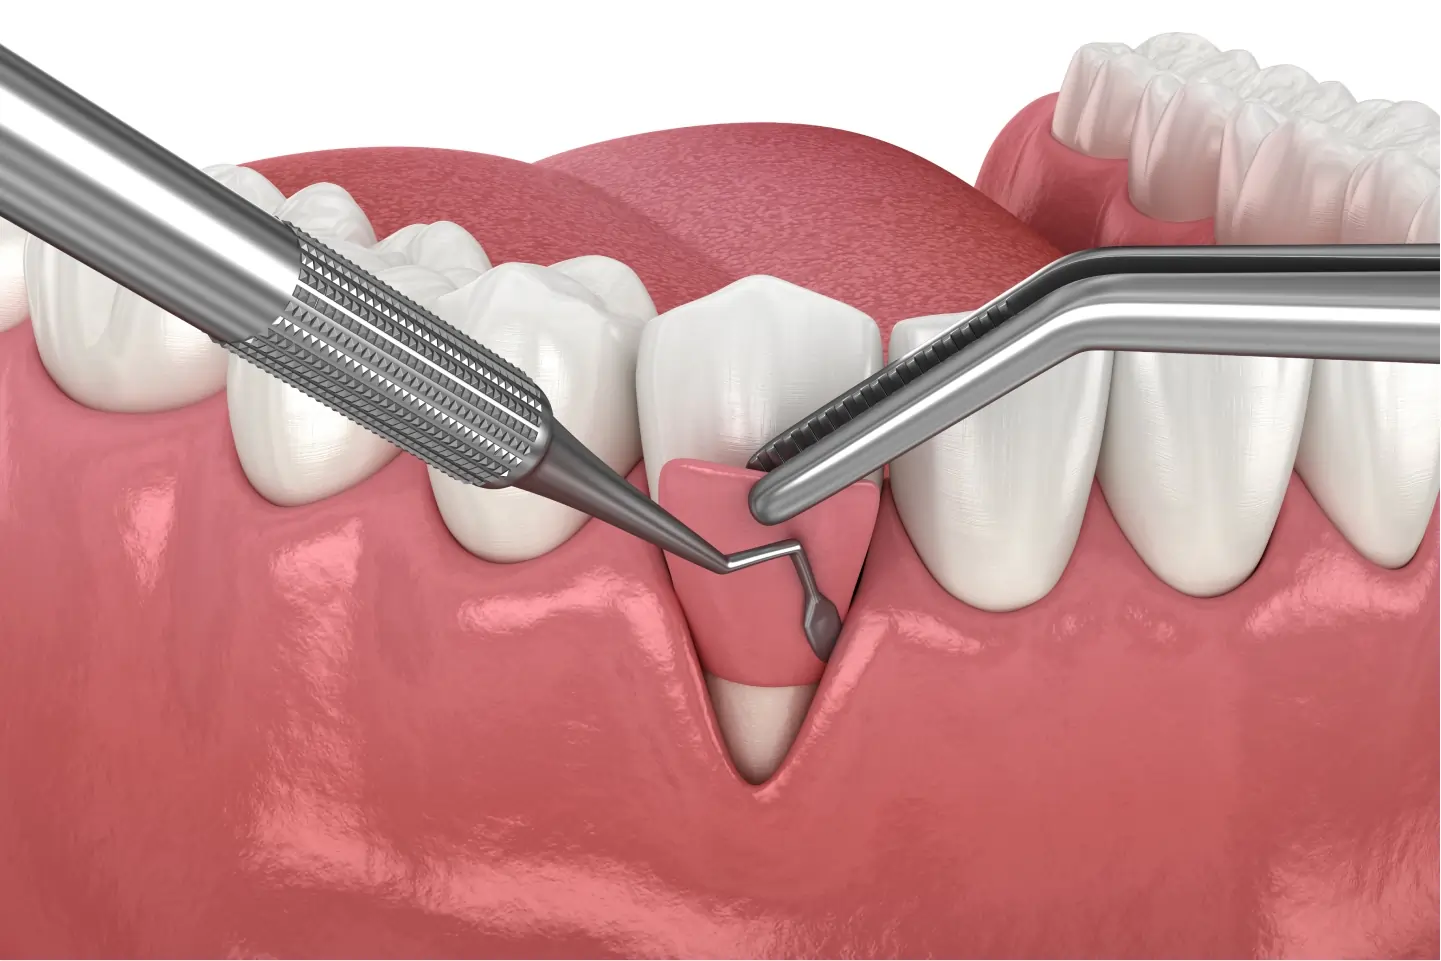

1. Pocket Reduction Surgery (Gingival Flap Surgery)

When gum disease progresses, it creates deep pockets between the gums and teeth, allowing bacteria to accumulate and cause further damage. Pocket reduction surgery helps by:

- Removing infected gum tissue

- Deep cleaning the roots to eliminate bacteria

- Reattaching healthy gum tissue to the tooth

This procedure prevents future infections and helps preserve the natural structure of the gums.